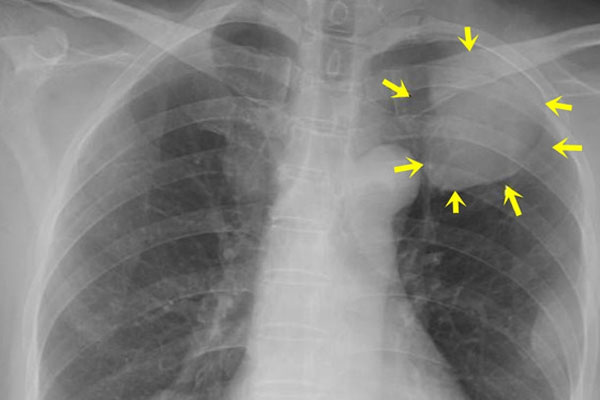

Trao đổi với Zing, bác sĩ Ngô Đức Tuấn, Giám đốc Bệnh viện Đa khoa Đồng Nai, cho biết tình trạng bệnh nhân này chuyển biến nặng. Ngoài viêm phổi, suy hô hấp phải thở máy, bệnh nhân còn bị nhiễm thêm vi khuẩn đa kháng thuốc. Bệnh nhân đáp ứng kháng sinh kém. Đến sáng 7/9, tình trạng của bệnh nhân có cải thiện nhưng tiên lượng còn nặng.

Sức cơ tay, chân của bệnh nhân chỉ còn 2/5. Người đàn ông này chỉ vận động được các đầu chi. Ông không thể di chuyển các chi ra khỏi giường bệnh. Ngoài ra, bệnh nhân bị suy hô hấp, phụ thuộc hoàn toàn vào máy thở.

Bệnh nhân bị ngộ độc botulinum trong pate Minh Chay đang điều trị Bệnh viện Chợ Rẫy. Ảnh: BVCC.